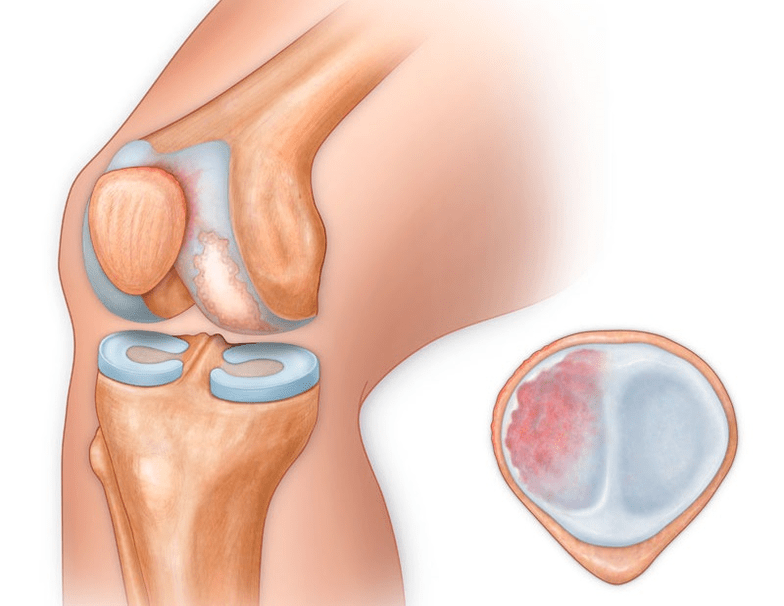

In addition to the inner or outer part of the knee, arthrosis can also affect the surfaces between the patella and the intercondylar groove of the femur.This option is calledpatellofemoral arthrosis.

This is usually caused by subluxation, fracture or lateralization of the patella.